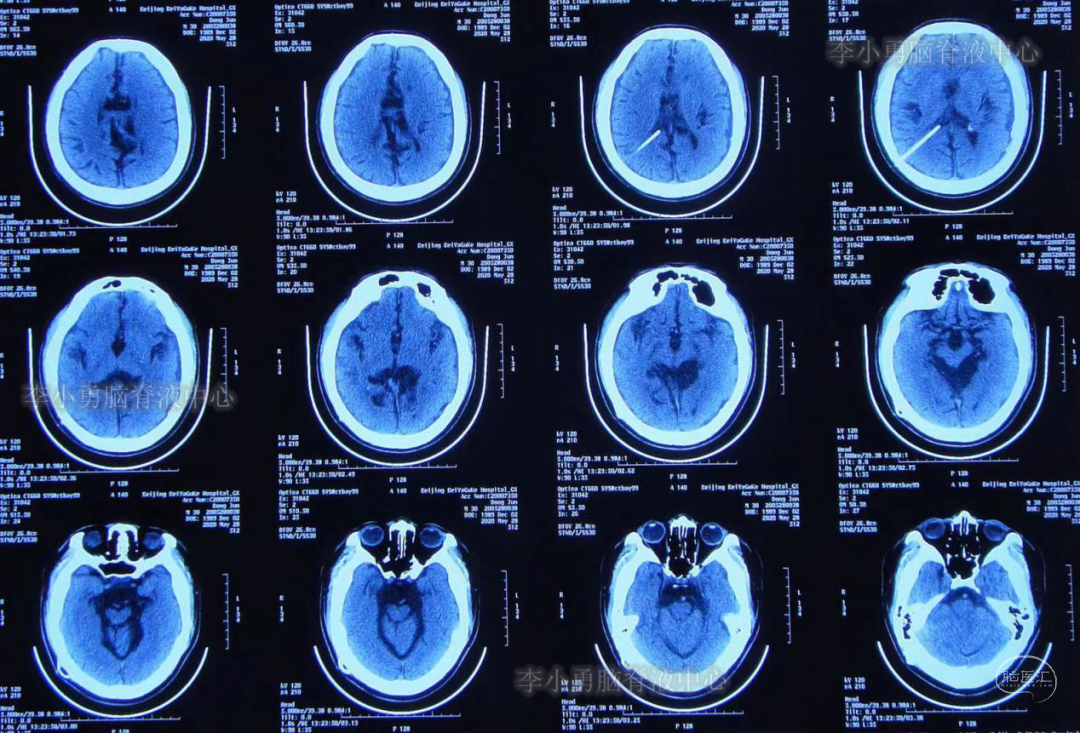

入院后第4天即2020年6月1日,行原脑室腹腔分流管拔除术+脑室外引流术,术后当日复查头部CT(图-5)。

图-5:2020年6月1日术后头CT